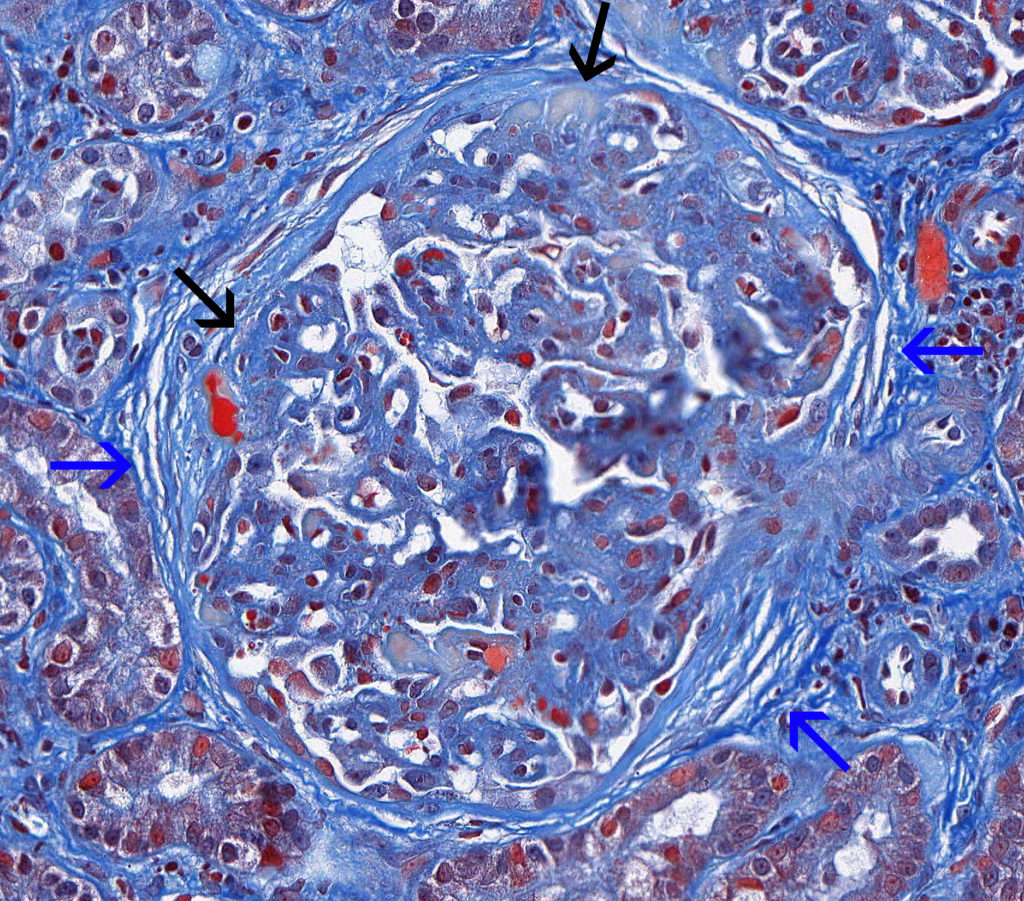

Механизм остро го диффузного гломерулонефрита